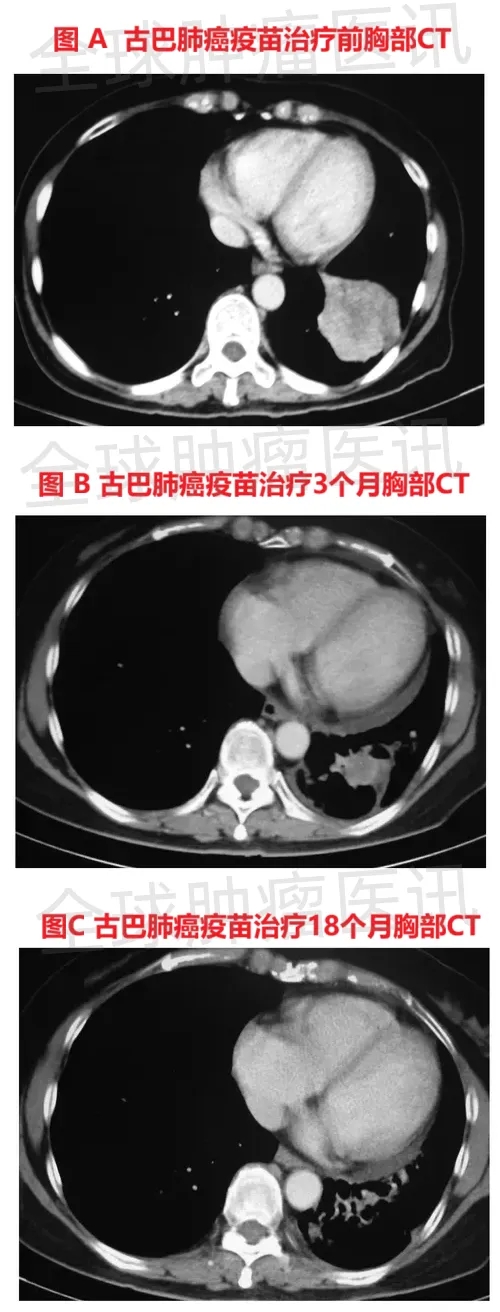

结果显示:疫苗治疗后的效果呈现出持续改善的趋势,治疗前的CT复查显示,患者左下叶病变已缩小至3cm×3cm(详见下图A),左上叶病变直径<1cm,同时存在放射治疗引发的包裹性胸腔积液;疫苗治疗3个月后,左下叶肿瘤进一步缩小至2cm×2.1cm(详见下图B);治疗6个月后,肿瘤体积降至1.5cm×2.3cm(详见下图C),较初始放化疗后的大小缩小30%,且后续趋于稳定,同期患者的胸腔积液减少、局部淋巴结缩小。

▲图源“Hum VaccImmunother”,版权归原作者所有,如无意中侵犯了知识产权,请联系我们删除

停止疫苗治疗3个月后(即疫苗治疗总时长18个月时),胸部CT显示肿瘤大小与6个月前相比“无明显变化”;在最后一次随访(停止疫苗注射28个月后)时,患者身体状况良好、健康状态稳定,ECOG体力状态评分始终维持在0分(代表完全正常活动,无体力限制)。